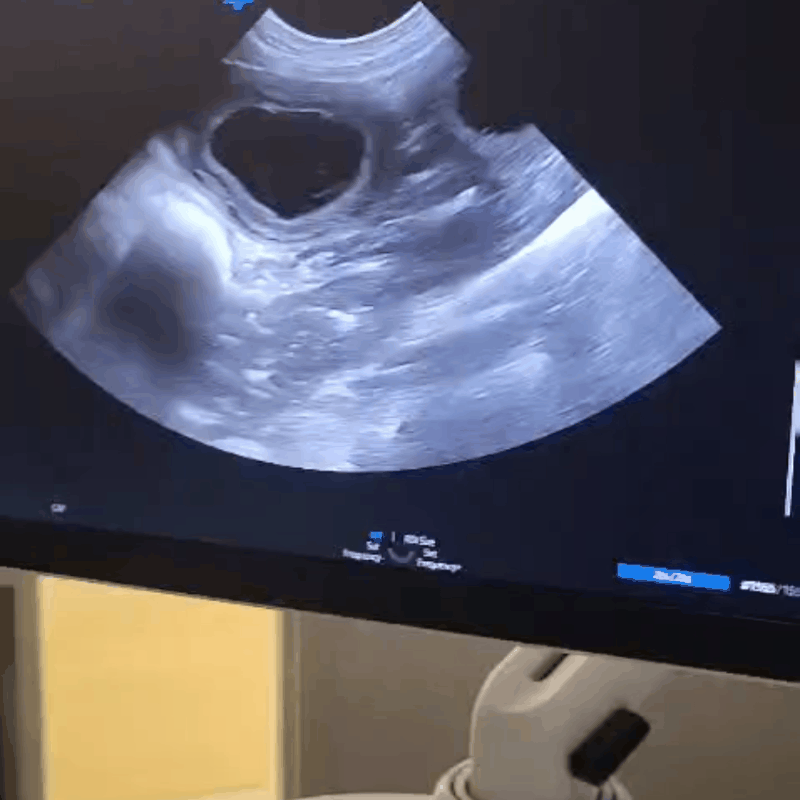

Echo en röntgenfoto!

Rond 30 juni heeft de dekking plaatsgevonden, en op 25 juni hebben we met een echo bevestigd dat ze inderdaad zwanger is.